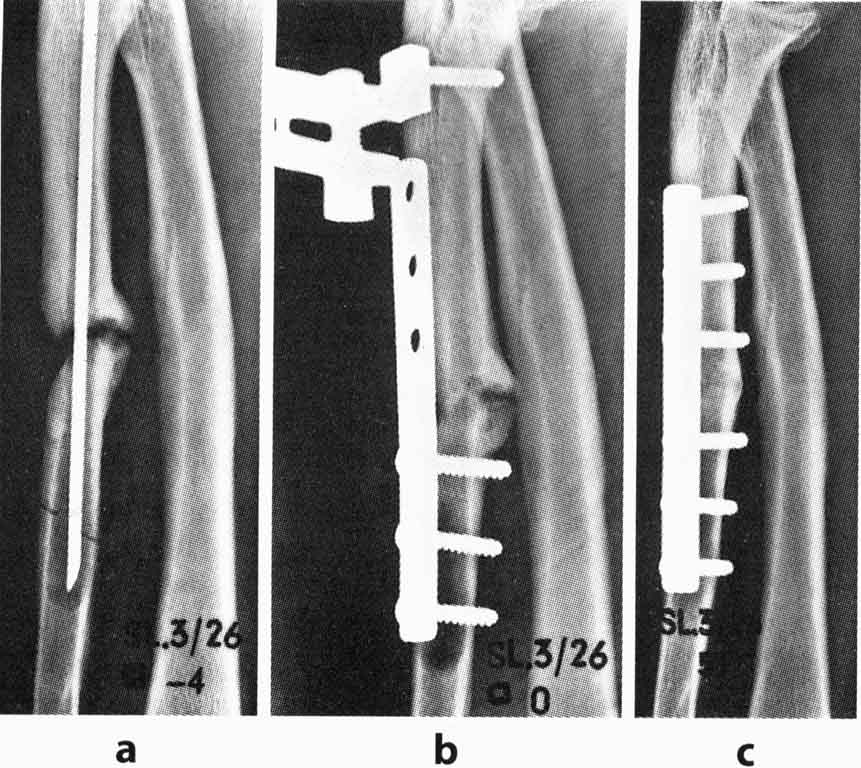

PS Напоследок – пример. Л.Г., 61 год, псевдоартроз локтевой кости после интрамедуллярной фиксации. Первичные документы утеряны (Рис. а), дефект и остеолизис. Стабилизация шести дырчатой пластиной, компрессия стягивающим устройством (Рис. в). Консолидация через год (Рис. с). Пример из Urs F.A. Heim. The AO Phenomenon. Foundation and early years of the Association for the Study of Internal Fixation.

Пример взят из книги, так как у меня таких давних примеров по вполне понятным причинам нет. И пластины у меня в картотеке более современные. Но, не хочу, что бы результат лечения ассоциировался с блокированием и так далее. Здесь главное – знание базовых принципов, элементарной техники и скрупулёзного следования этому. Данная операция была выполнена в 1962 году. Для лечения данной патологии ничего более нового и не потребуется. Сможете?